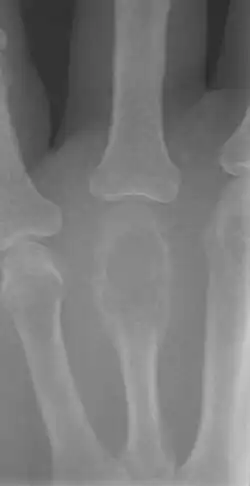

Aanvullend onderzoek

- Röntgenfoto van het bot